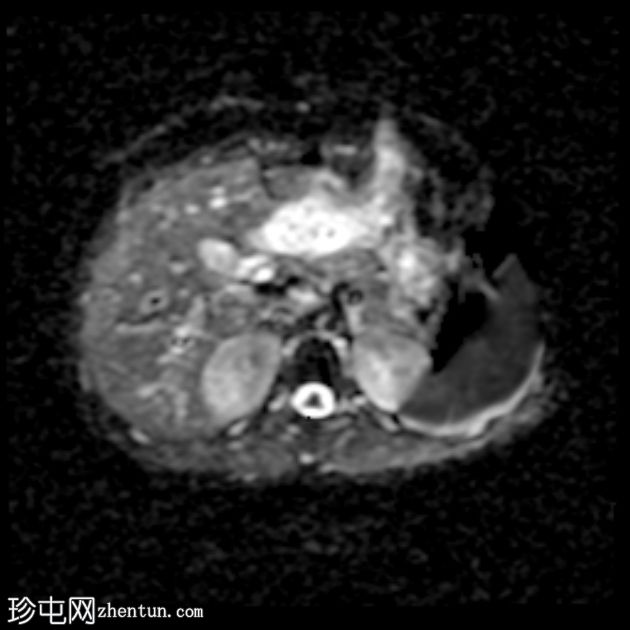

轴位

ADC序列

子宫前倾位,分区解剖结构正常。矢状位序列可见子宫前壁肌层局灶性边界不清的低信号病灶,但在后续序列中未见明显,符合短暂的生理性子宫肌层收缩表现。

双侧卵巢大小及卵泡活动均正常。未见囊性或实性肿块。

该病例的盆腔器官MRI表现与患者年龄(14岁)相符,子宫位置正常,分区解剖结构正常,双侧卵巢大小及卵泡活动均正常,未见囊性或实性肿块。

此外,MRI还意外发现子宫肌层局灶性病变,T2信号低,易被误诊为子宫肌瘤。然而,该病变在后续序列中消失,符合短暂的生理性子宫肌层收缩所致。